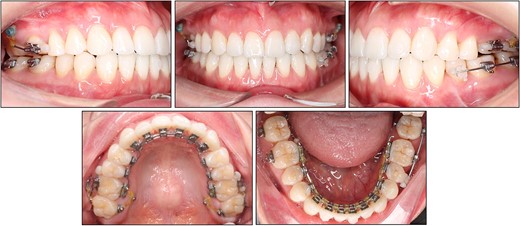

After treatment, class I canine and molar relationships were obtained on both sides with a normal overjet and positive overbite (Fig. 5). The posttreatment lateral cephalometric evaluation showed an improvement in both anteroposterior (point A-nasion-point B angle, 3.1°) and vertical dimensions (Frankfort mandibular angle, 31.0°). The posttreatment panoramic radiograph showed adequate root parallelism without any sign of root resorption (Fig. 6). The lateral cephalometric superimpositions confirmed the intrusion of the maxillary molars, the extrusions of the incisors, and the counter-clockwise autorotation of the mandible (Fig. 7).

Bonded lingual retainers were placed in both arches along with clear retainers for night-time use. The patient was evaluated at a 2-year follow-up and the treatment results remained stable (Fig. 8). The patient expressed satisfaction with the treatment, citing both the resolution of the chief complaint and the invisible nature of the appliances.